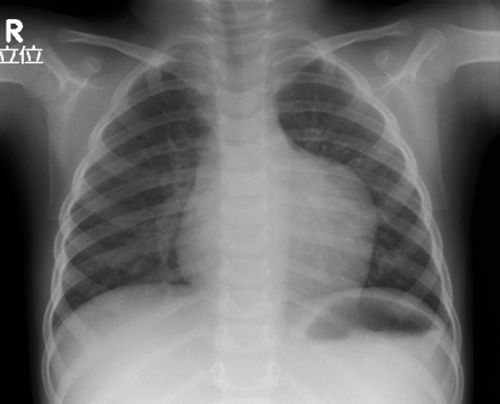

無症候性左心耳瘤の病理組織学的検討Histopathological Findings of Asymptomatic Left Atrial Appendage Aneurysm